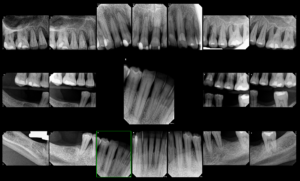

What is an FMX?

Patients are often curious about the kinds of x-rays we take, and how we use them. FMX, pano, PA, bitewing, ceph, CBCT, these are various